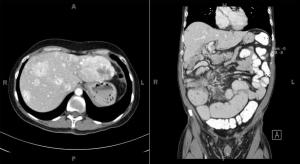

A 56-year-old woman presents with abdominal fullness and virilization. Axial and coronal images from a CT scan of her abdomen are shown below. What is your diagnosis?